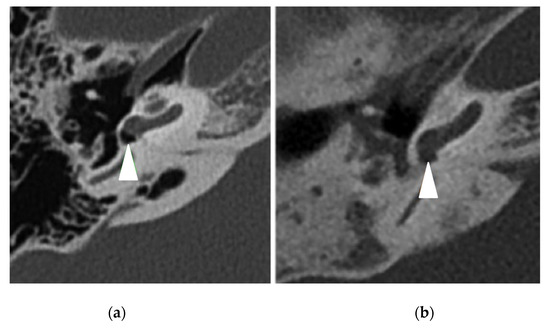

| Abnormal CT scan, | 32 (94%) | 11 (32%) | <0.0001 |

| Mastoid opacification | 13 (38%) | 8 (24%) | 0.19 |

| Mastoid condensation | 21 (62%) | 8 (24%) | 0.01 |

| Middle ear inflammation | 22 (65%) | 7 (21%) | 0.0002 |

| Ossicular anomaly | 12 (35%) | 3 (9%) | 0.01 |